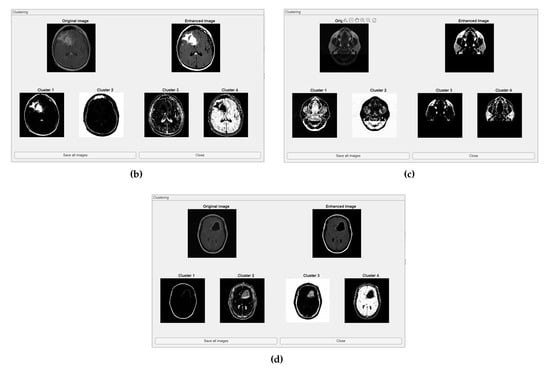

The comparative charts and visual presentation of edges allow for a detailed analysis of each algorithm’s strengths and weaknesses, offering insight into the trade-offs between edge completeness and false detection rates. Figure 4 illustrates the fuzzy C-means (FCM) clustering results obtained from the four case studies: CS1, CS2, DU1, and DU2. Each subfigure (A, B, C, and D) presents the following sequence:

-

Original Image: The initial input image from the dataset.

Enhanced Image: The result after applying image enhancement techniques to improve contrast and feature visibility, likely to support better clustering outcomes.

Clusters 1 to 4: The segmentation outputs, where the image has been partitioned into four distinct clusters. Each cluster highlights different regions based on pixel similarity, potentially corresponding to anatomical structures, tissues, or specific features of interest within the medical images.

Key Observation: Figure 4 and Figure A1 collectively showcase the clustering module’s capacity to aid in visual discrimination and structural interpretation across the studied medical cases.

Figure 4. Clustering with fuzzy C-means (FCM) results within iMIA platform: The clusters emphasize various structural and textural components, with some clusters isolating specific regions with clear edges and others focusing on more homogeneous areas. The segmentation reveals critical areas with varying intensity patterns, possibly indicative of different tissue types or pathological regions: TCGA_CS_4941_19960909_3 (CS1) (additional results are shown in Figure A1).

Figure A1. Clustering with fuzzy C-means (FCM) results within iMIA platform. (b) TCGA_CS_4941_19960909_14 (CS2), (c) TCGA_DU_5872_19950223_1 (DU1), (d) TCGA_DU_5872_ 19950223_35 (DU2) (refer to the image (a) CS1 result in Figure 4).